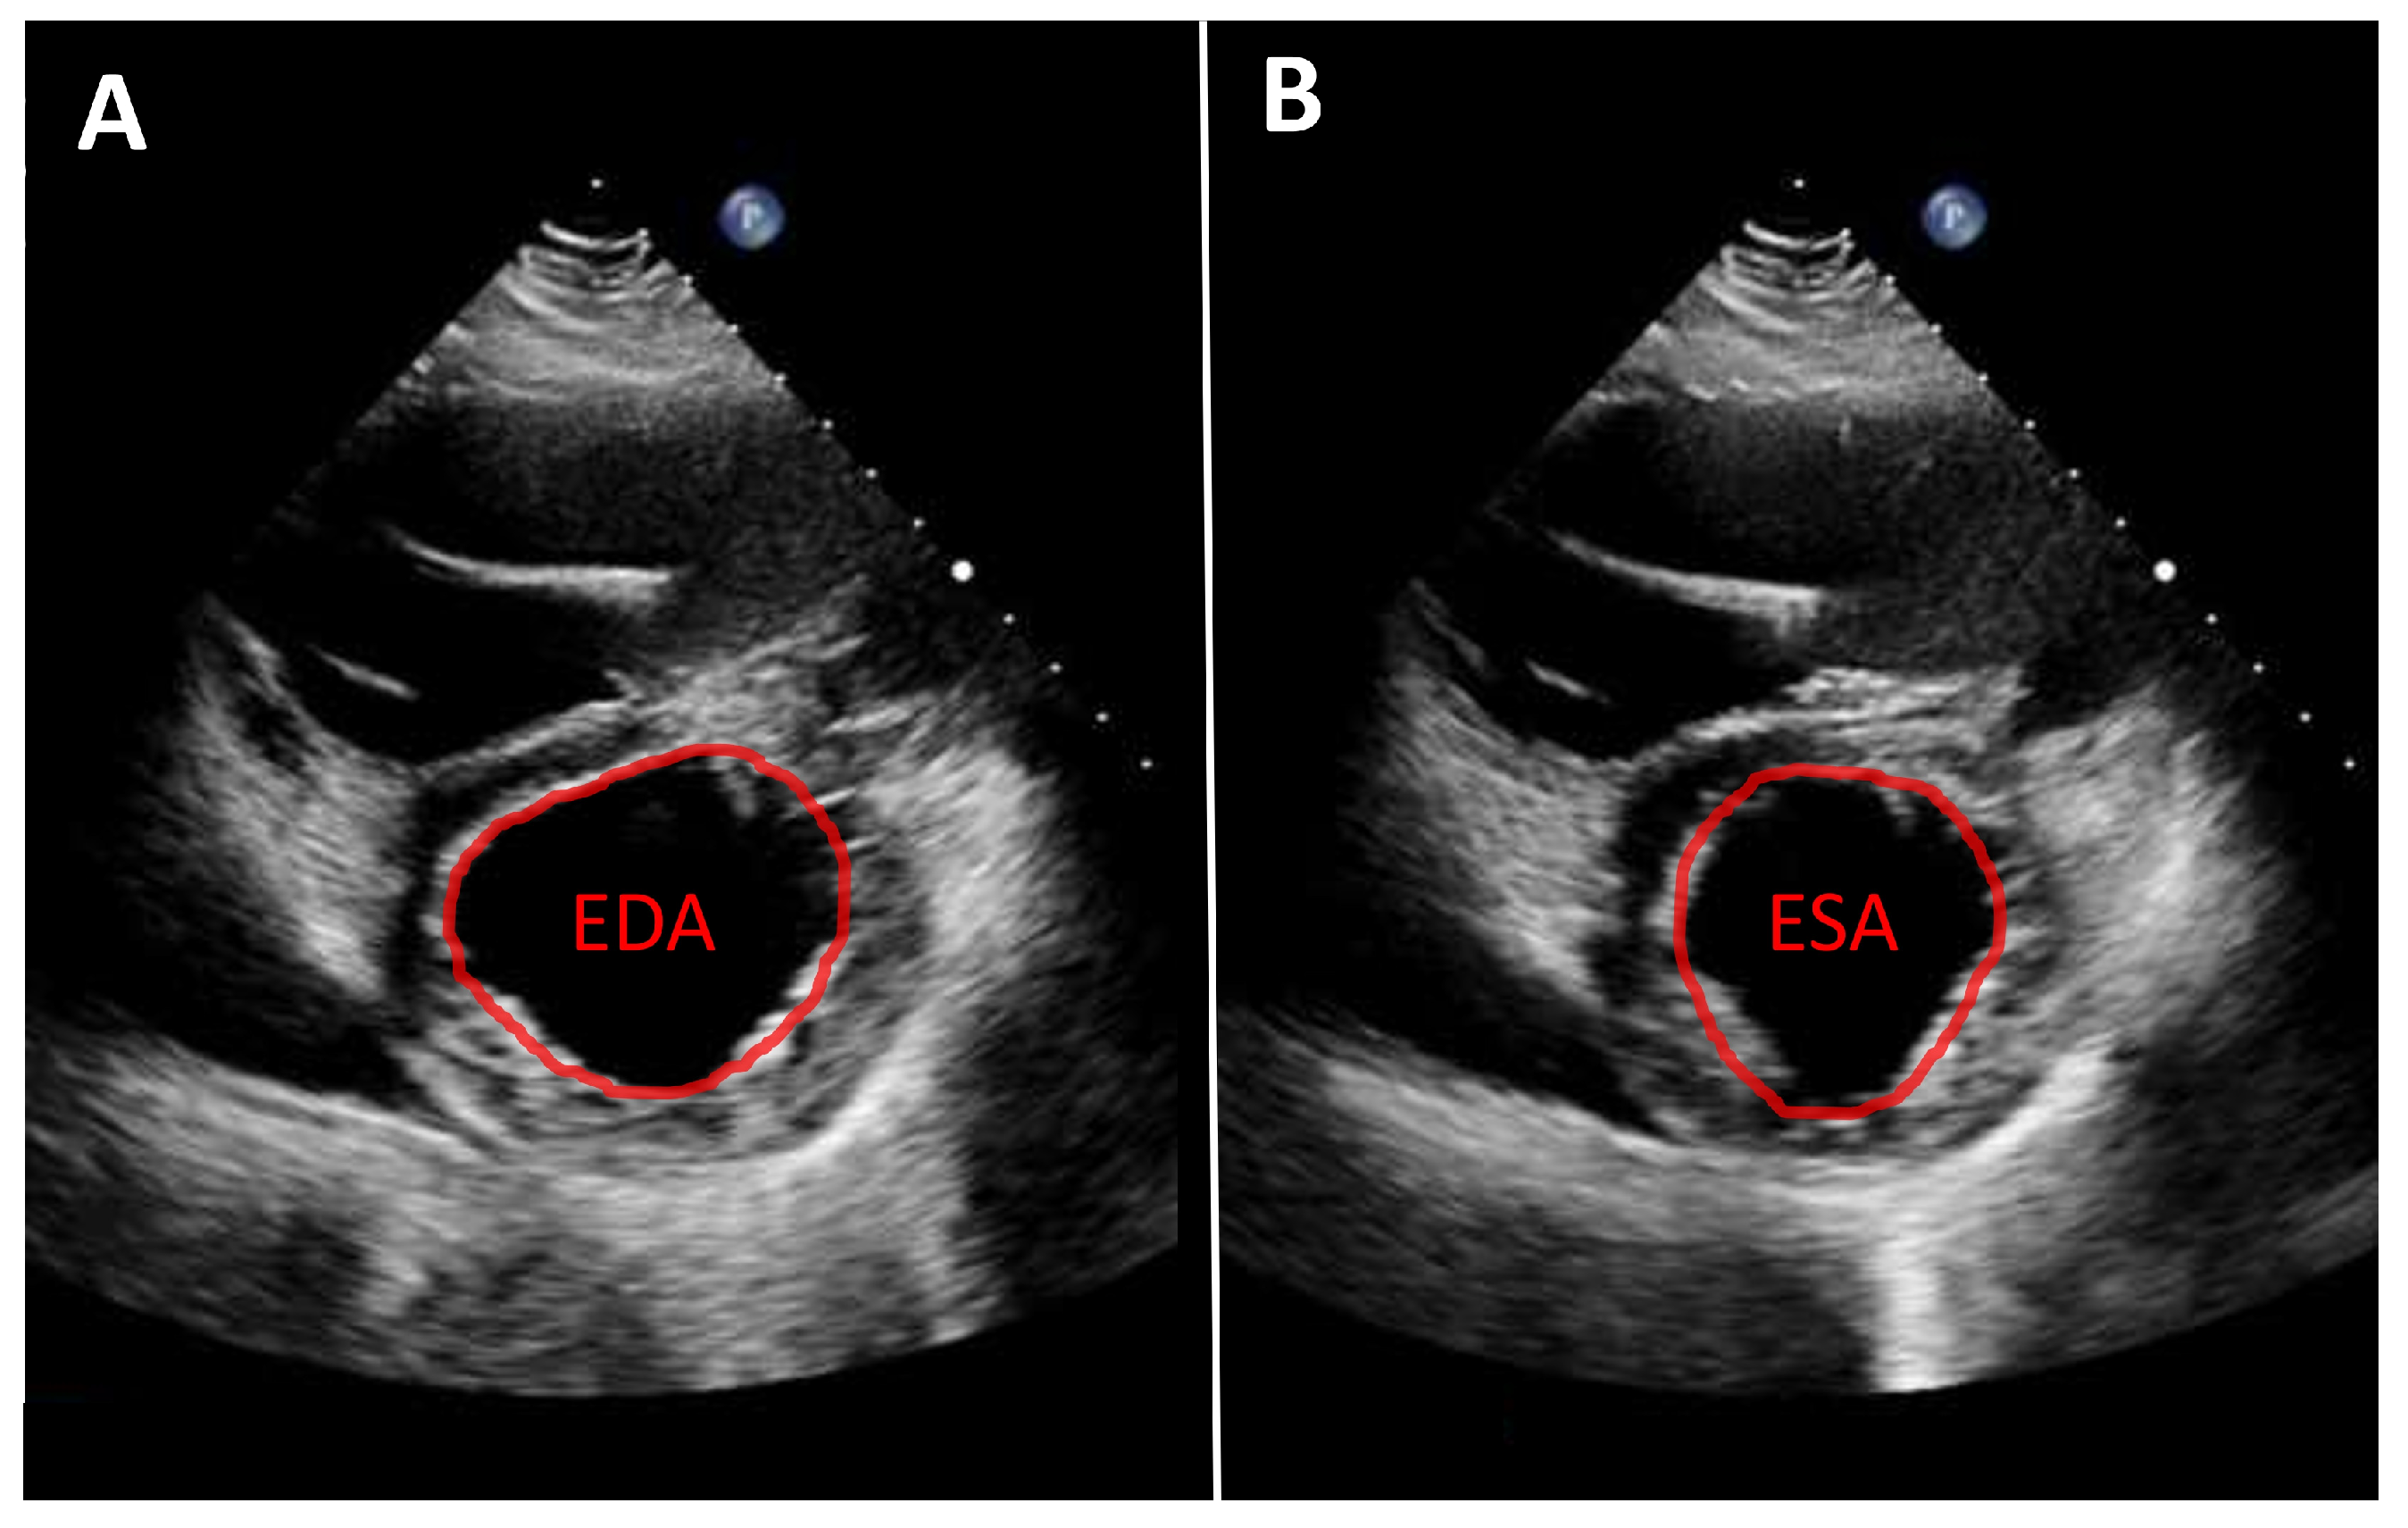

As noted above, left ventricular size should primarily be assessed using linear measurements. Implantation of a continuous-flow LVAD is typically associated with progressive left ventricular unloading and a corresponding reduction in ventricular size. While mean left ventricular end-diastolic diameter (LVEDD) reduction of approximately 1 cm has been reported, the magnitude of this change varies substantially between individual patients [7,10]. A substantial reduction in left ventricular diameter is often associated with a leftward septal shift and may occur in the context of excessive left ventricular unloading. Left ventricular function can likewise only rarely be quantified from apical views. Consequently, volumetric determination of ejection fraction as well as assessment of global longitudinal strain are usually not feasible. Therefore, linear measurements, such as fractional shortening, obtained from the parasternal long-axis view, are recommended. An even more accurate assessment, which is also frequently feasible, is measurement of left ventricular fractional area change in the parasternal short-axis view (Figure 1). Mild improvements in left ventricular function after LVAD implantation are frequently observed [7,10,11]. More substantial recovery of left ventricular function has been reported in a small but clinically relevant subset of patients [8,12,13]. In such cases, following comprehensive evaluation using dedicated testing and standardized weaning protocols, LVAD explantation may be considered.

Figure 1.

Parasternal short-axis view. Measurement of fractional area change (FAC) in a patient with an LVAD. (A): Planimetry of the end-diastolic area (EDA). (B): Planimetry of the end-systolic area (ESA). Calculation of FAC: FAC = (EDA − ESA)/EDA.